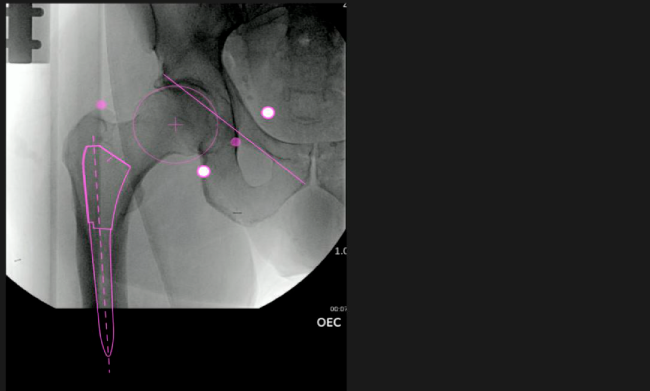

Nuestro navegador de cadera VELYS HIP NAVIGATION ™ es una solución digital que te acompañará a mejorar cada paso de las fases operatorias.

El sistema de navegación digital VELYS HIP NAVIGATION ™ para cirugía de cadera, es una tecnología innovadora y no invasiva diseñada para potencializar la toma de decisiones en tiempo real y basada en datos; aumentando la precisión y mejorando los resultados a corto, mediano y largo plazo para los pacientes.

Planeación preoperatoria mediante la creación de plantillas digitales para reemplazo de cadera y análisis intraoperatorio

Aumenta la precisión y reproducibilidad quirúrgica generando resultados predecibles.

Datos procesables en tiempo real para la toma de decisiones.